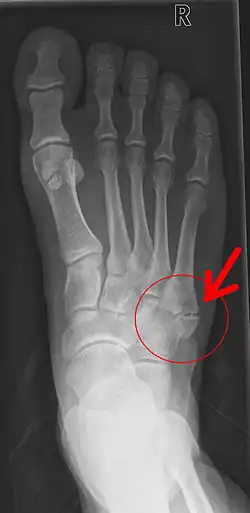

Pseudarthrose

Une pseudarthrose est une « fausse » articulation d'un os à l'endroit d'une fracture résultant de la cicatrisation indépendante des pièces de la fracture.

On parle plus précisément de pseudarthrose en cas de persistance du trait de fracture plus de 6 mois après la lésion initiale.